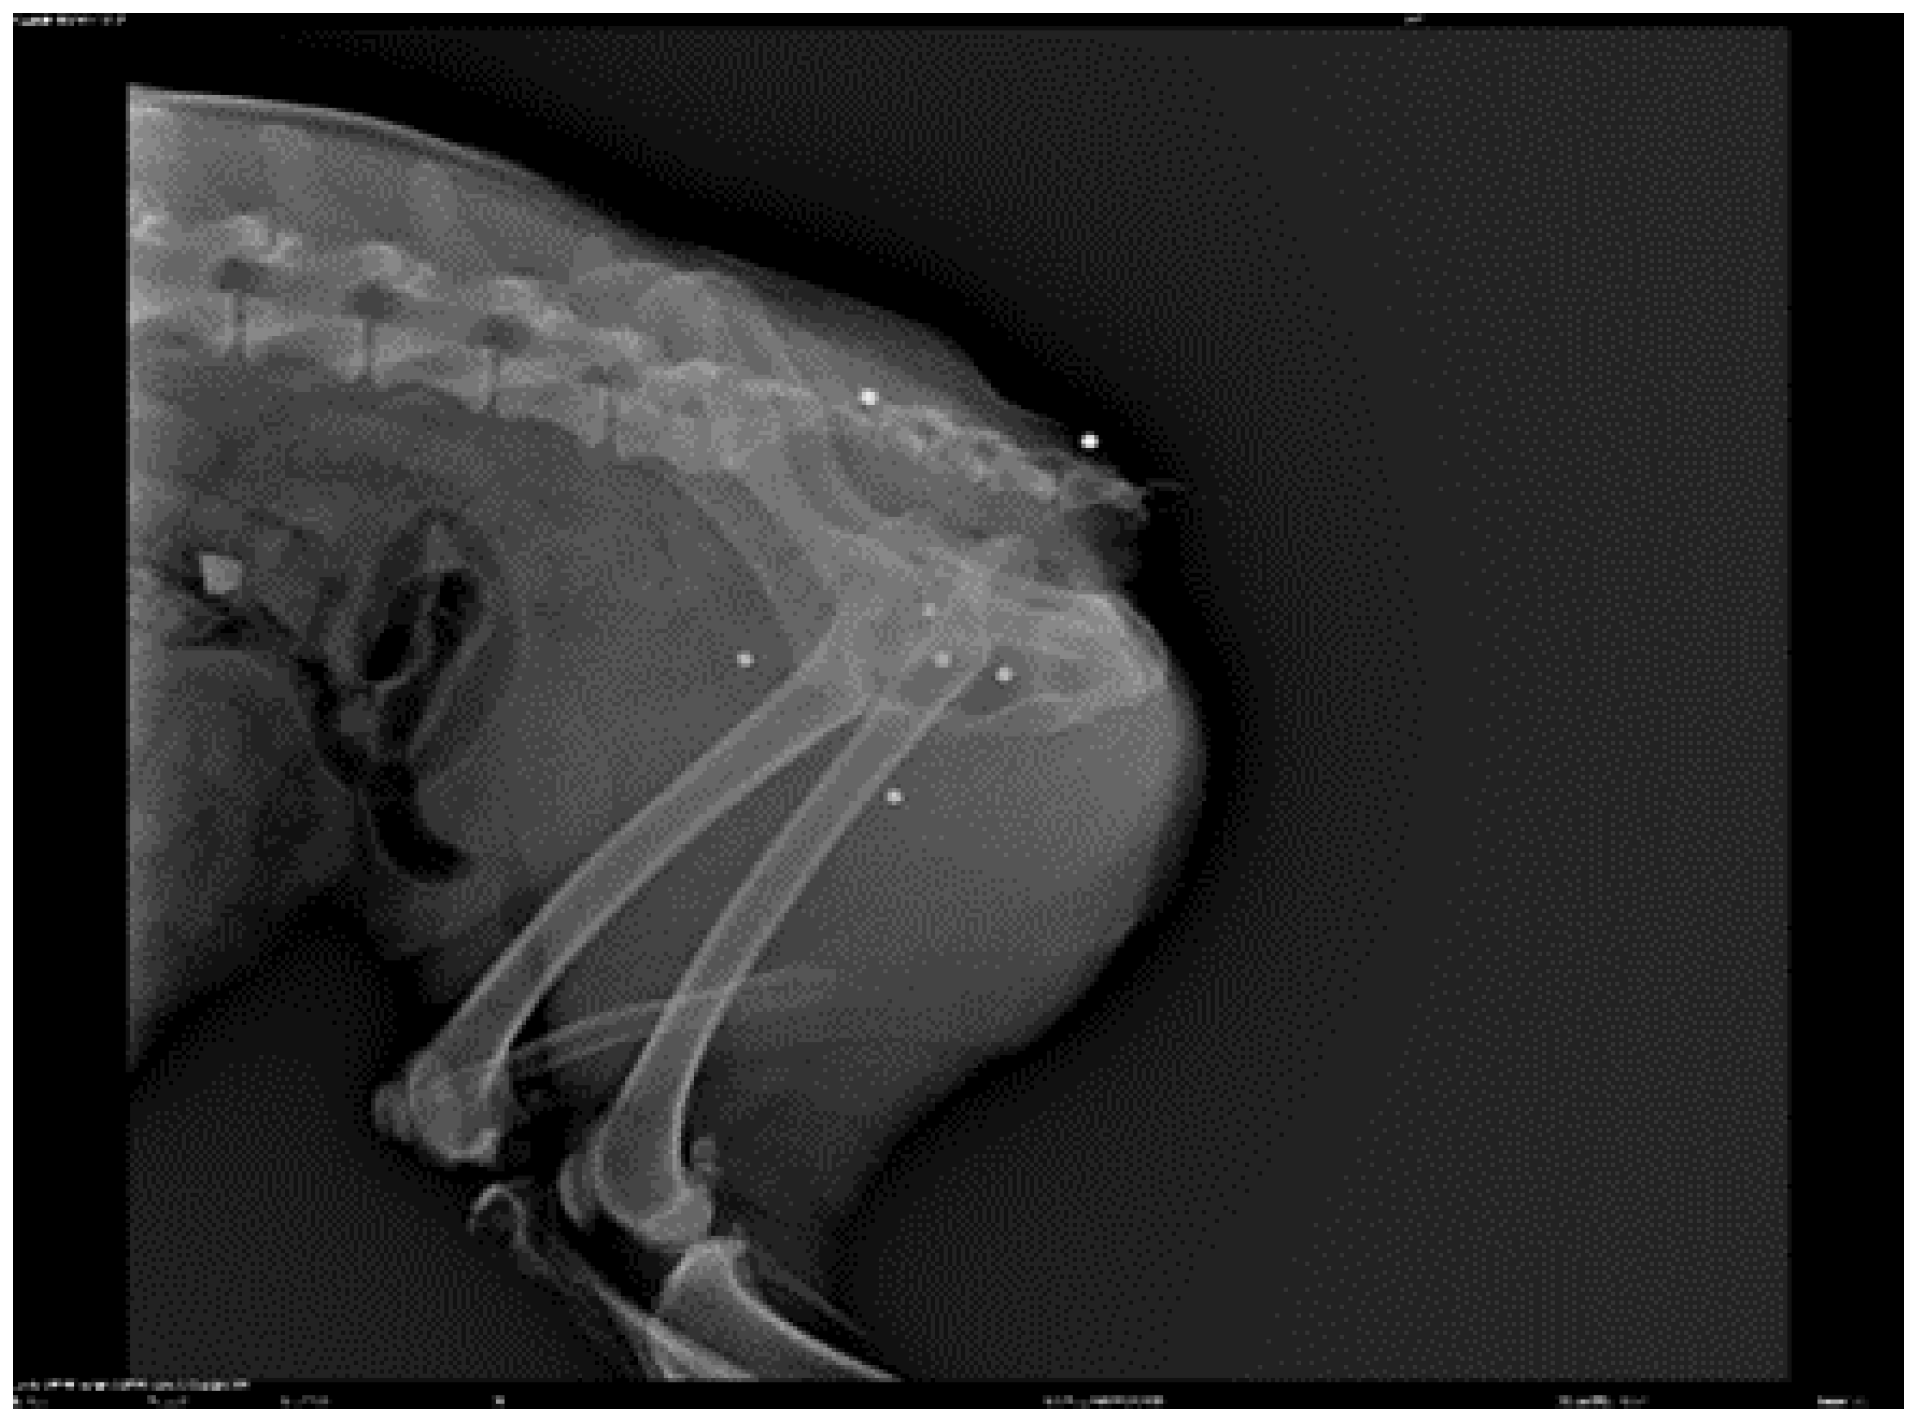

![]() |